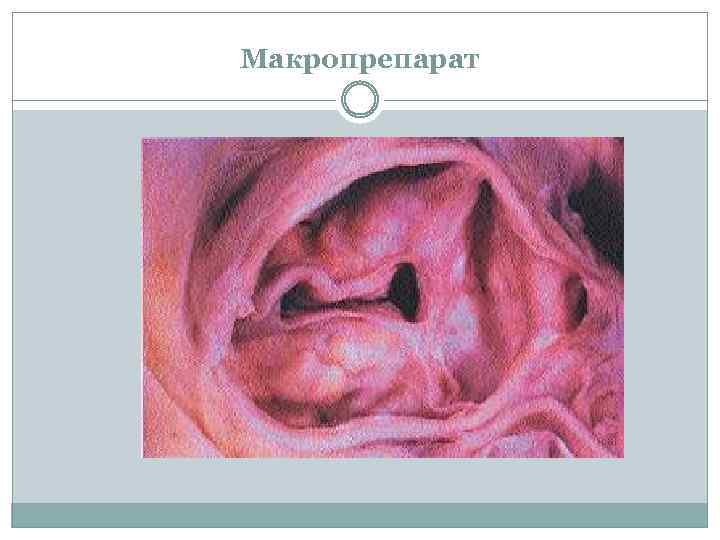

Макропрепарат